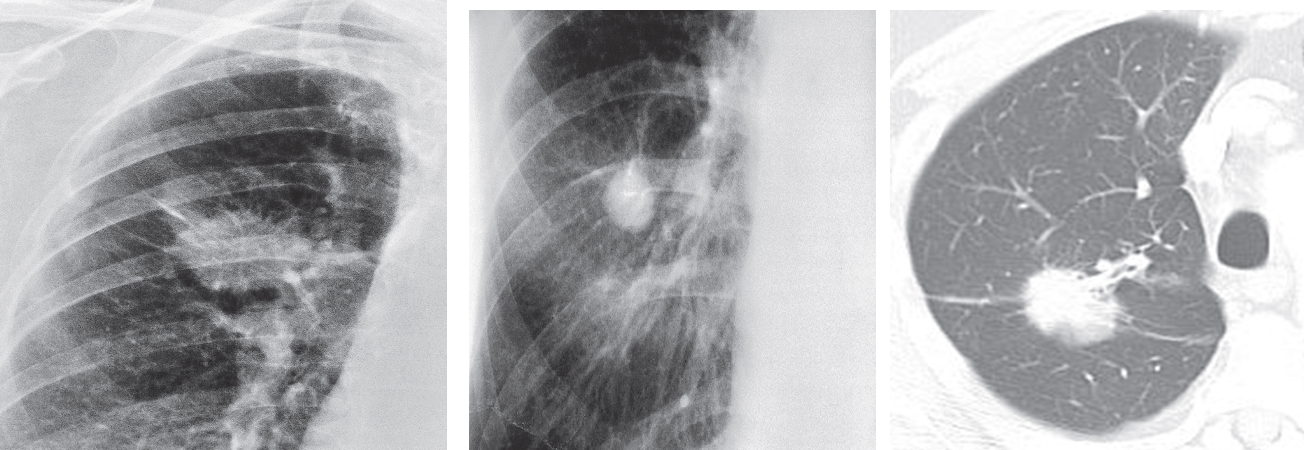

The large size and the irregular infiltrating edge are important diagnostic features suggesting primary carcinoma of the lung. (b) small size & relatively smooth border leads to a wider differential diagnosis. (c) Typical bronchial carcinoma on CT showing an infiltrating edge.